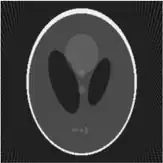

If a function represents an unknown density, then the Radon transform represents the projection data obtained as the output of a tomographic scan. Hence the inverse of the Radon transform can be used to reconstruct the original density from the projection data, and thus it forms the mathematical underpinning for tomographic reconstruction, also known as iterative reconstruction.

The process of reconstruction produces the image (or function in the previous section) from its projection data. Reconstruction is an inverse problem.

Iterative reconstruction methods

Compared with the Filtered Back-projection method, iterative reconstruction costs large computation time, limiting its practical use. However, due to the ill-posedness of Radon Inversion, the Filtered Back-projection method may be infeasible in the presence of discontinuity or noise. Iterative reconstruction methods (e.g. iterative Sparse Asymptotic Minimum Variance[10]) could provide metal artefact reduction, noise and dose reduction for the reconstructed result that attract much research interest around the world.

Thus in an image processing context the original image can be recovered from the 'sinogram' data by applying a ramp filter (in the variable) and then back-projecting. As the filtering step can be performed efficiently (for example using digital signal processing techniques) and the back projection step is simply an accumulation of values in the pixels of the image, this results in a highly efficient, and hence widely used, algorithm. Explicitly, the inversion formula obtained by the latter method is:[4]